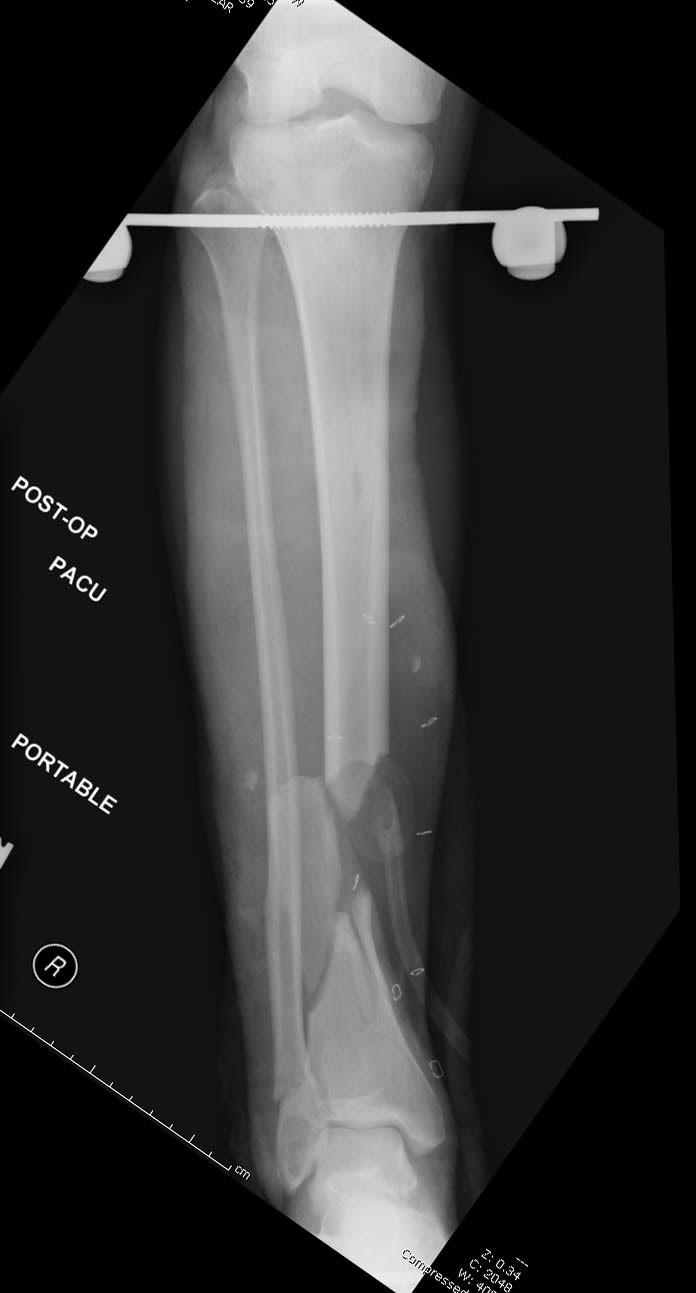

Данный случай не огнестрельная рана, а результат мотоциклетной аварии.

Независимо от повреждения при таких обширных дефектах мягких и костной

тканей применяется схожая тактика. Как видно, после нескольких I&D для

создания “pseudo membrane” применили цилиндрический блок из цемента.

Дефект мягких тканей закрыли свободным Anterior Thigh Graft. Из малого

доступа цилиндр удален небольшими кусочками, а пространство заполнили

бусами для освобождения пространства. По мере приближения регенерата

освободили пространство удалением бус через небольшой разрез. Этап

созревание регенерата можно было ускорить усилением интрамедуллярным

гвоздем, но решили закончить методом Илизарова.